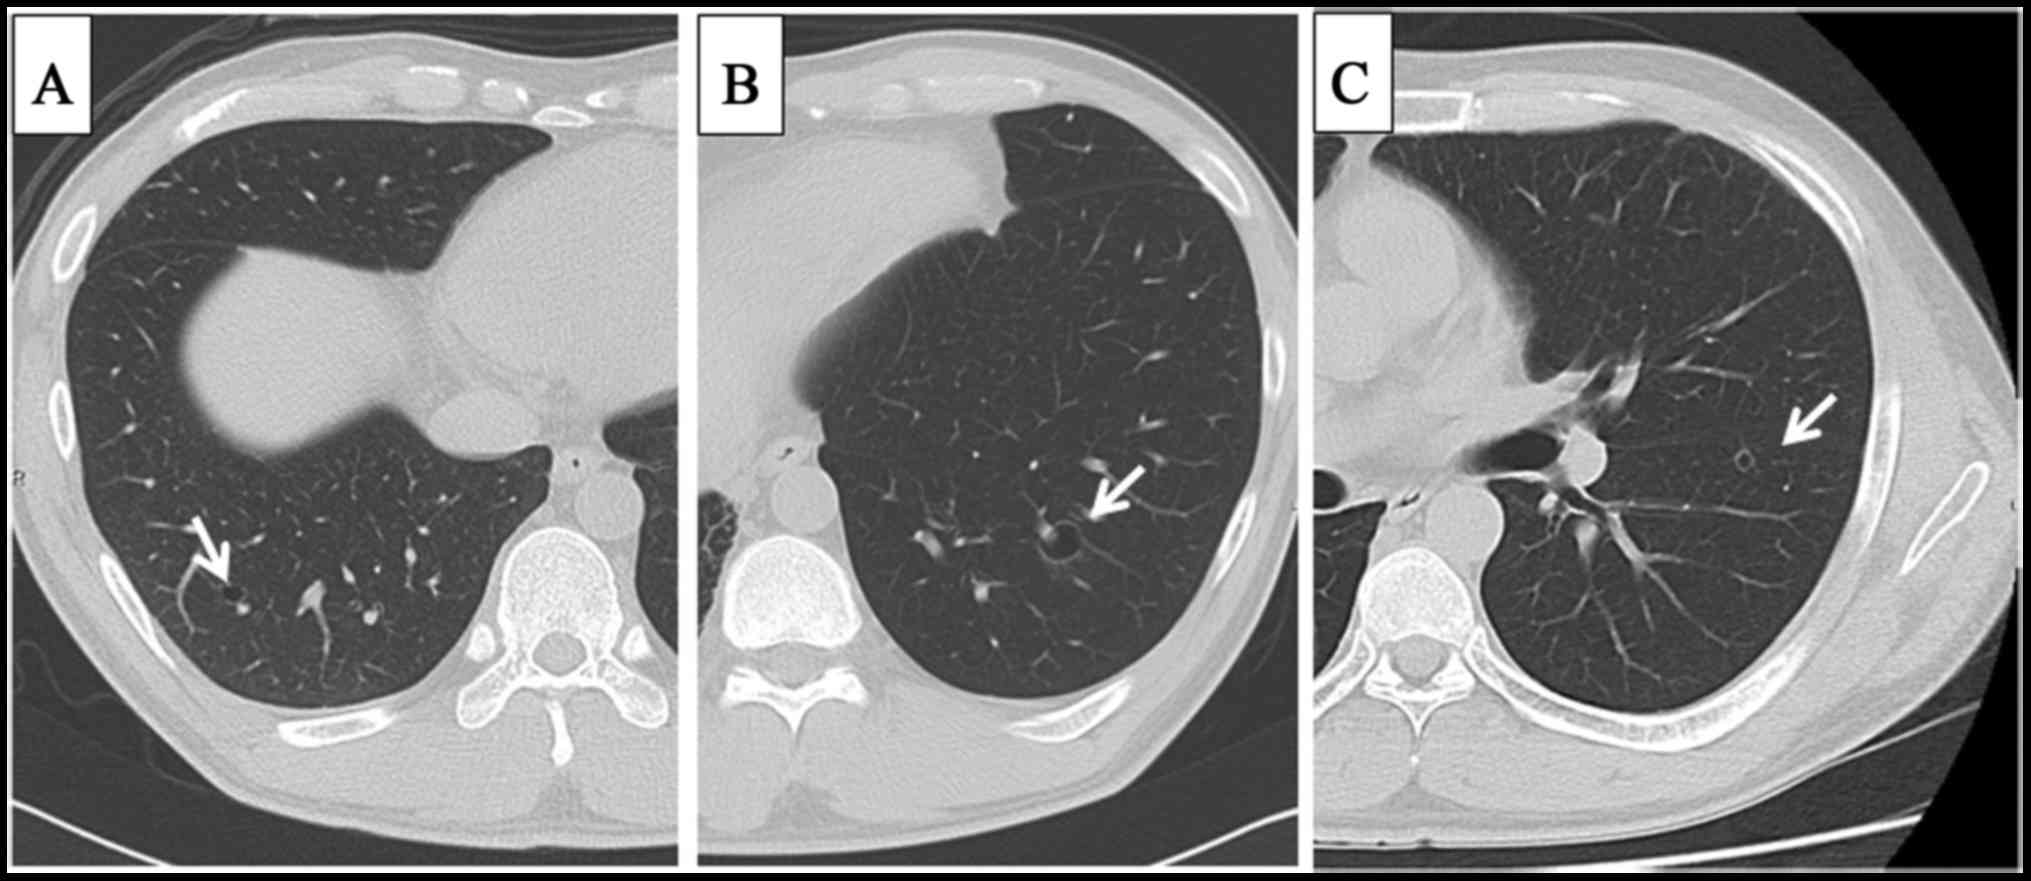

A 33-year old man presented with sudden dyspnea and chest pain on the left side. The patient had undergone wide resection of an epithelioid sarcoma in the left forearm (Fig. 1) and pre- and post-operative chemotherapy treatment 6 years prior. Four years ago, he complained of continuous bloody sputum. A solid nodule of sarcomatous metastasis appeared in the right lung, and histological examination via bronchoscopy confirmed the pulmonary metastases from the epithelioid sarcoma (Fig. 2). Following histological confirmation, he started receiving repeated chemotherapy treatments, composed of doxorubicin (DOX; 60 mg/m2)/ifosfamide (IFM; 10 g/m2), ifosfamide (IFM; 15 g/m2), docetaxel (DTX; 75 mg/m2)/gemcitabine (GEM; 900 mg/m2), and methotrexate (MTX; 10 g/m2). Despite repeated chemotherapy treatments, multiple small, thin-walled cystic metastases in bilateral lungs appeared on computed tomography (CT) examination (Fig. 3), and the number and size of cystic metastases increased in 4 years.

Figure 3.

Pulmonary computed tomography demonstrated cystic pulmonary metastases (white arrows) in the right lung (A) and left lung (B and C).

In our patient, the cystic lesion was not evident on chest radiograpy, but was well visible with CT. CT has been shown to be more sensitive in the detection of small metastatic foci. Small cystic pulmonary lesions are also best visualized with CT. Cystic change associated with primary lung cancer is relatively frequent. Cystic pulmonary metastases usually form a thin smooth wall similar to an emphysematous bulla or a pneumatocele (2). The accurate differential diagnosis of a cavity metastasis from a benign bulla and primary lung cancer is critically important. Metastatic tumor nodules are easily recognizable when many solid tumor nodules are also present. When few or no solid lesions are seen, however, cavity tumor nodules must be differentiated from primary lung cancer, primary benign cystic pulmonary disease (2,11,12). Ultimately, the detailed pathological diagnosis is mandatory to determine a cystic change in sarcoma.